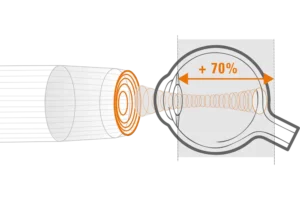

Verlengde scherptediepte van 70%

De ringtechnologie verdubbelt praktisch de scherptediepte. De 20 MHz-ringvormige sonde heeft een verlengde scherptediepte van 70%, waardoor het mogelijk is om pathologieën van het glasvocht, het netvlies en verder tegelijkertijd te observeren zonder concessies te doen aan de beeldresolutie.